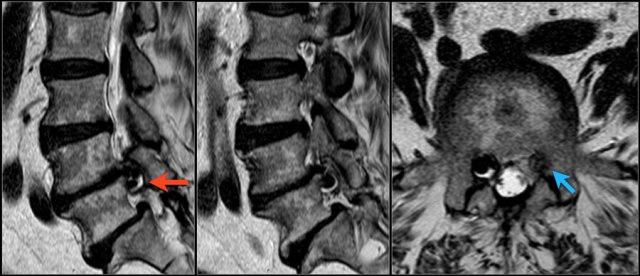

Here a patient with severe arthrosis of the facet joints.

Notice that there are many synovial cysts related to the arthrosis (red arrows).

At the L5S1 level a large cyst on the right compresses the S1-nerve (yellow arrow).